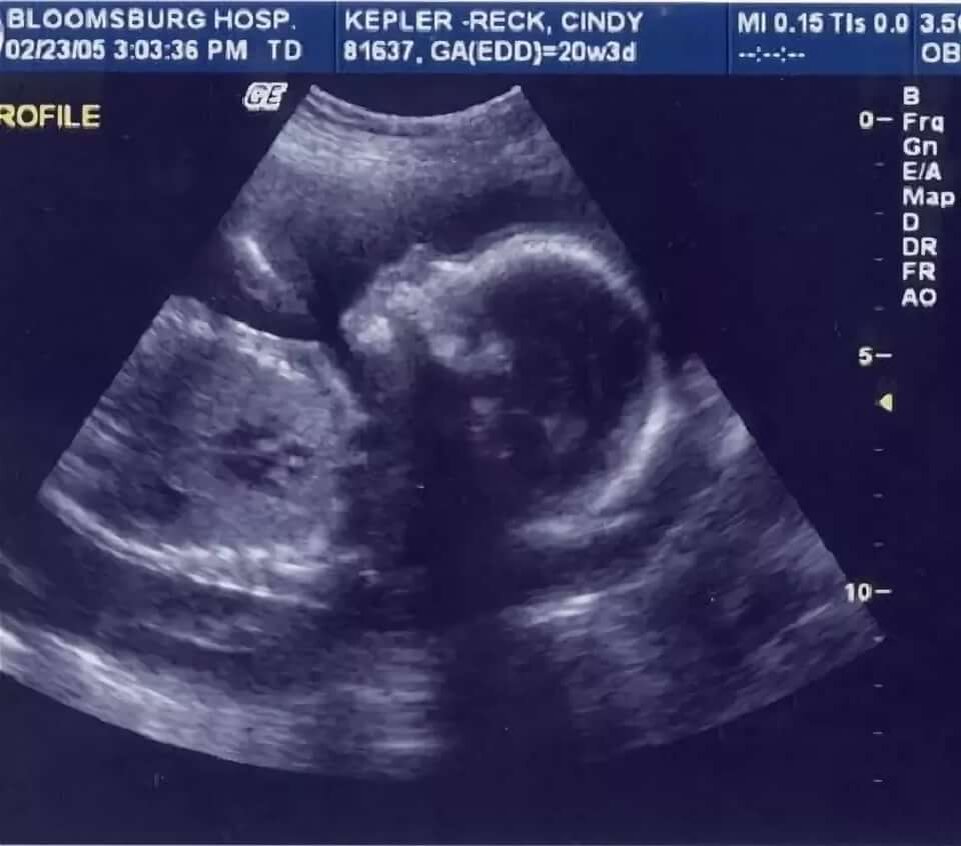

То, что врачи увидели на УЗИ было шокирующе!

Ребёнок всё это время развивался в неправильном месте, а точнее, в брюшной полости! Женщину срочно отправили в больницу с направлением на операцию.